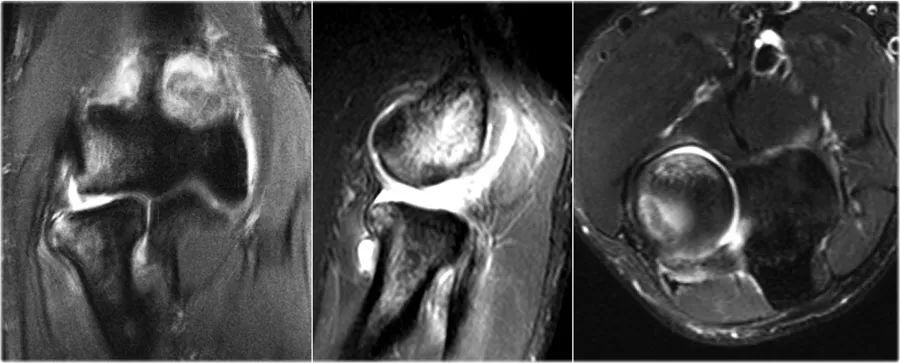

外翻过度综合征的关节病由于外翻过载,在肱骨-尺骨关节的后内侧部分存在剪切力。注意在T1W图像上看到的软骨下硬化(红色箭头)。在T2W图像上存在软骨下骨髓水肿和软骨损失(黄色箭头)。